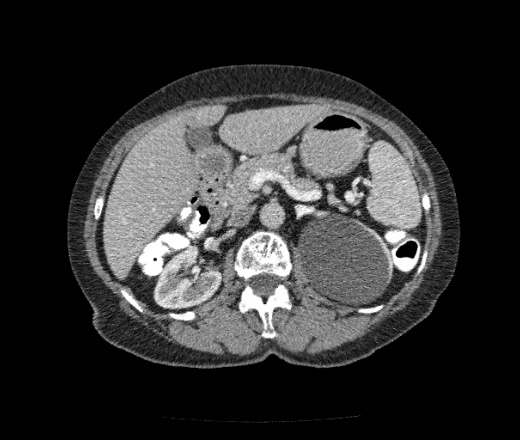

Впечатление, что дуля эта вне головки п.ж., интрамурально в луковице, что ли... тогда возможно GIST, но надо дайком. Утолщение подслизистой в антральном отделе желудка, не удается проследить переход от желудка к 12-перстной((. Внутрипросветно/внутристеночно - не разобрать. 1 фаза?

Клинику! Есть ли признаки высокой тонкокишечной непроходимости, что при ФЭГДС в 12-перстной - туда удалось пройти или нет? ААА! Одни вопросы))))

В-общем, варианты такие без дайкомов: пролапс слизистой в 12перстную, безоар, внутрипросветный дивертикул, гастроинтерстинальная опухоль. И большие сомнения, что это в головке п.ж. - оно отделено от неё тонким слоем жировой клетчатки

Фаз было 3. Видео не выставлял прошлый раз пришел ответ из сайта что видео не работает на сайте Идет накопление контраста в нативе в центре +2+4 по периферии +32+34 .в артериальную +20 и +65 +70 соответственно.

Что оно копит - бог с ним... если это пролапс слизистой, то суммация стенок. Безоар бы не копил. Напрягает отек слизистой в антрале... Это должно быть скорее внутри просвета кишки, т.к. оттесняет газ в 12-перстной на периферию. Без дайкомов больше ничем не могу, извините. Подождём мнения коллег.

Как мне видится - пролапс слизистой желудка в 12-перстную. А мнения коллег что-то нетути...

А что растет из левой почки? Может оно же и желудок сдавливает?

Это расширение всей 12- перстной кишки (стаз).

Посмотрите видео, только верхняя треть и расширена.